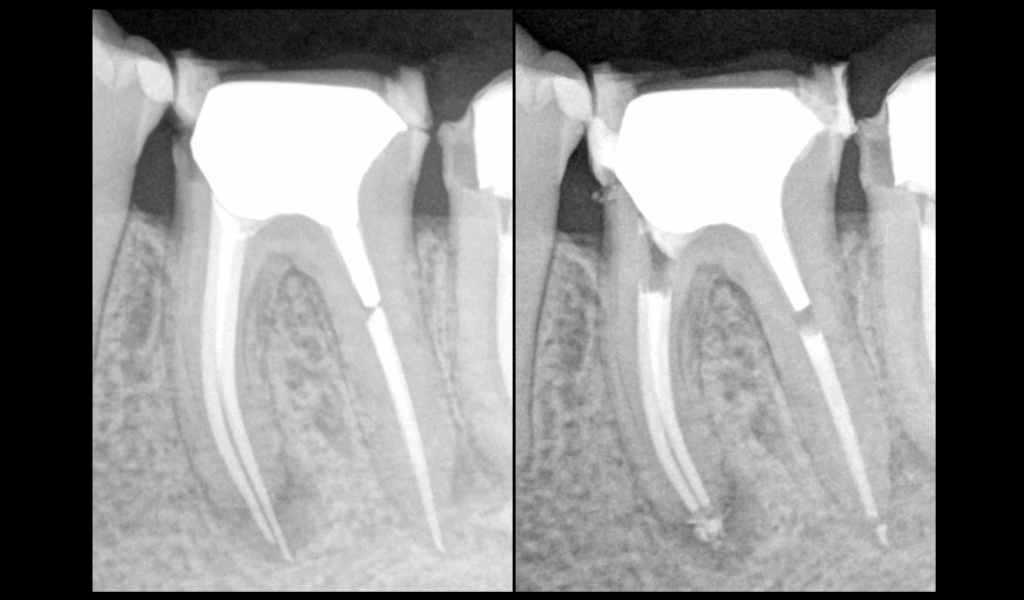

❓ Quel protocole pour désobturer ce dépassement de gutta ?

📌 𝐃𝐚𝐧𝐬 𝐜𝐞 𝐜𝐚𝐬 :

🖐️ Désobturation manuelle

📏 Obtention de la LT

⚙️ Instrumentation mécanisée :

• Race 10.04 (pas EVO)

• 15.04 (EVO)

• 25.04 (EVO)

• XP Shaper